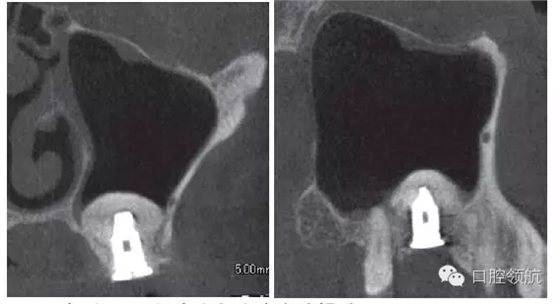

因為垂直骨量少,在植入種植體后,為防止種植體進入上頜竇內(nèi),選擇了安裝直徑大的覆蓋螺絲(圖5、圖6)。 術(shù)后CBCT證實上頜竇底提升了足夠的骨量(圖7)。

圖7 術(shù)后CBCT證實上頜竇底充分提升。

術(shù)后12周在獲得骨結(jié)合后,開始制作上部結(jié)構(gòu),術(shù)后16周戴入(圖8)。術(shù)后24周,CBCT影像顯示,種植體周圍有足夠的骨量(圖9)。

圖9 術(shù)后24周,CBCT影像顯示通過拔牙后早期植入,能夠進行安全確實的上頜竇底提升術(shù)。